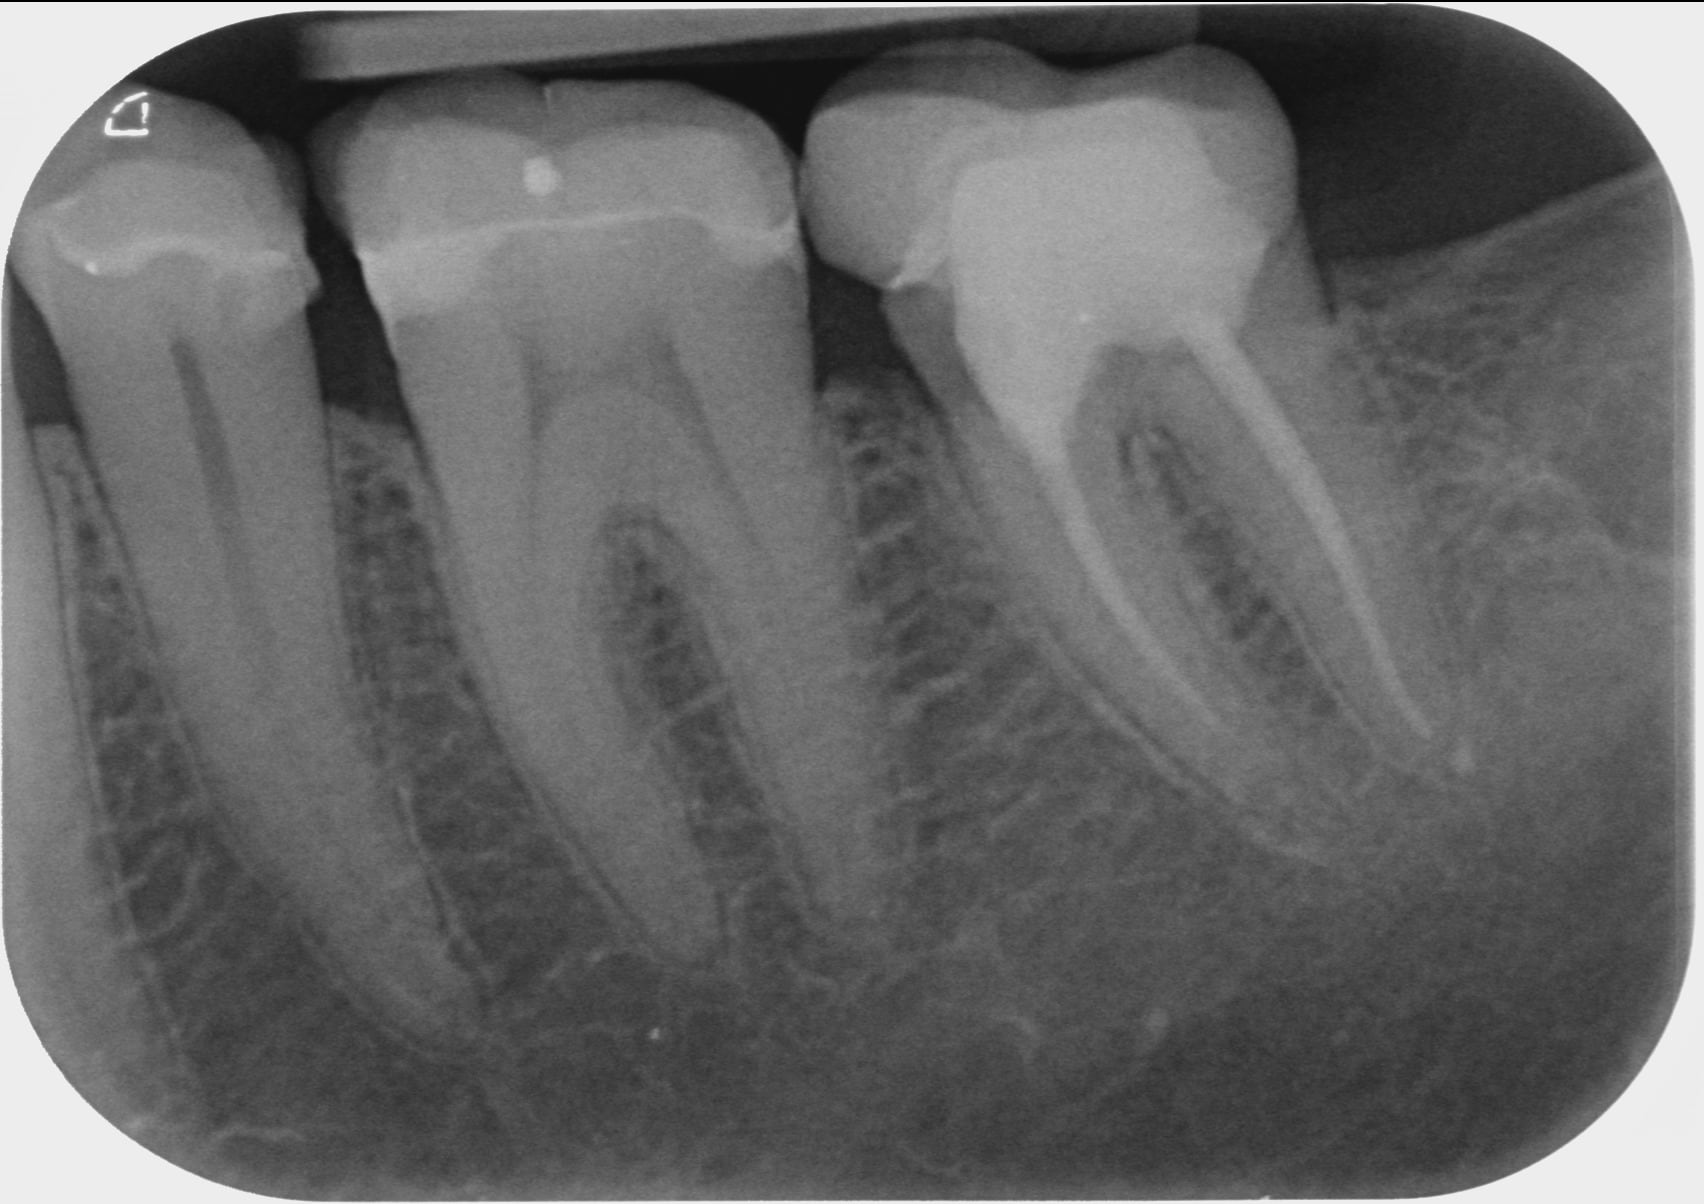

J'ai une dernière demande puisque Tozzi m'a fait un peu peur. Effectivement l'endo de la 37...n'est pas optimal..puisque ce n'est pas comblé jusqu'à l'apex..je pense que mon boss (qui met du temps à chaque fois à faire des endos avec digue dentaire) a fait de son mieux.

Tozzi..m'indique que je peux avoir une lésion qui ne se voit pas..et pense qu'il serait judicieux de la refaire. Mon boss...va me dire qu'il ne peut pas faire mieux.

Mais voter avis à tous car d'autre praticiens dont l'occluso..me disent non...pas d'infection.....je suis paumée du coup..

cette zone me titillant épisodiquement depuis 2 ans..si c'était en lien avec cette mauvaise étancheité..j'aurais au moins une tache noire sur la radio ?

bref.il ya-t-il urgence à reprendre cette endo (via exclusif sans doute)..ou non j'attend de voir avec la gouttière ?

Ben il suffit de comparer l’apex mésial et distal. sur le distal on suit parfaitement le desmondonte, sur le mésial c’est plus flou. Perso j’ai un CBCT au cabinet et c’est l’indication d’un examen au niveau de cette zone. Un champ de 5x5 avec une bonne colimation suffit pour se faire une idée sans une irradiation de folie et éliminer une ostéite à ce niveau , ça permettrait sans doute, aussi, de se faire aussi une idée sur la 26 et un éventuel MV2.